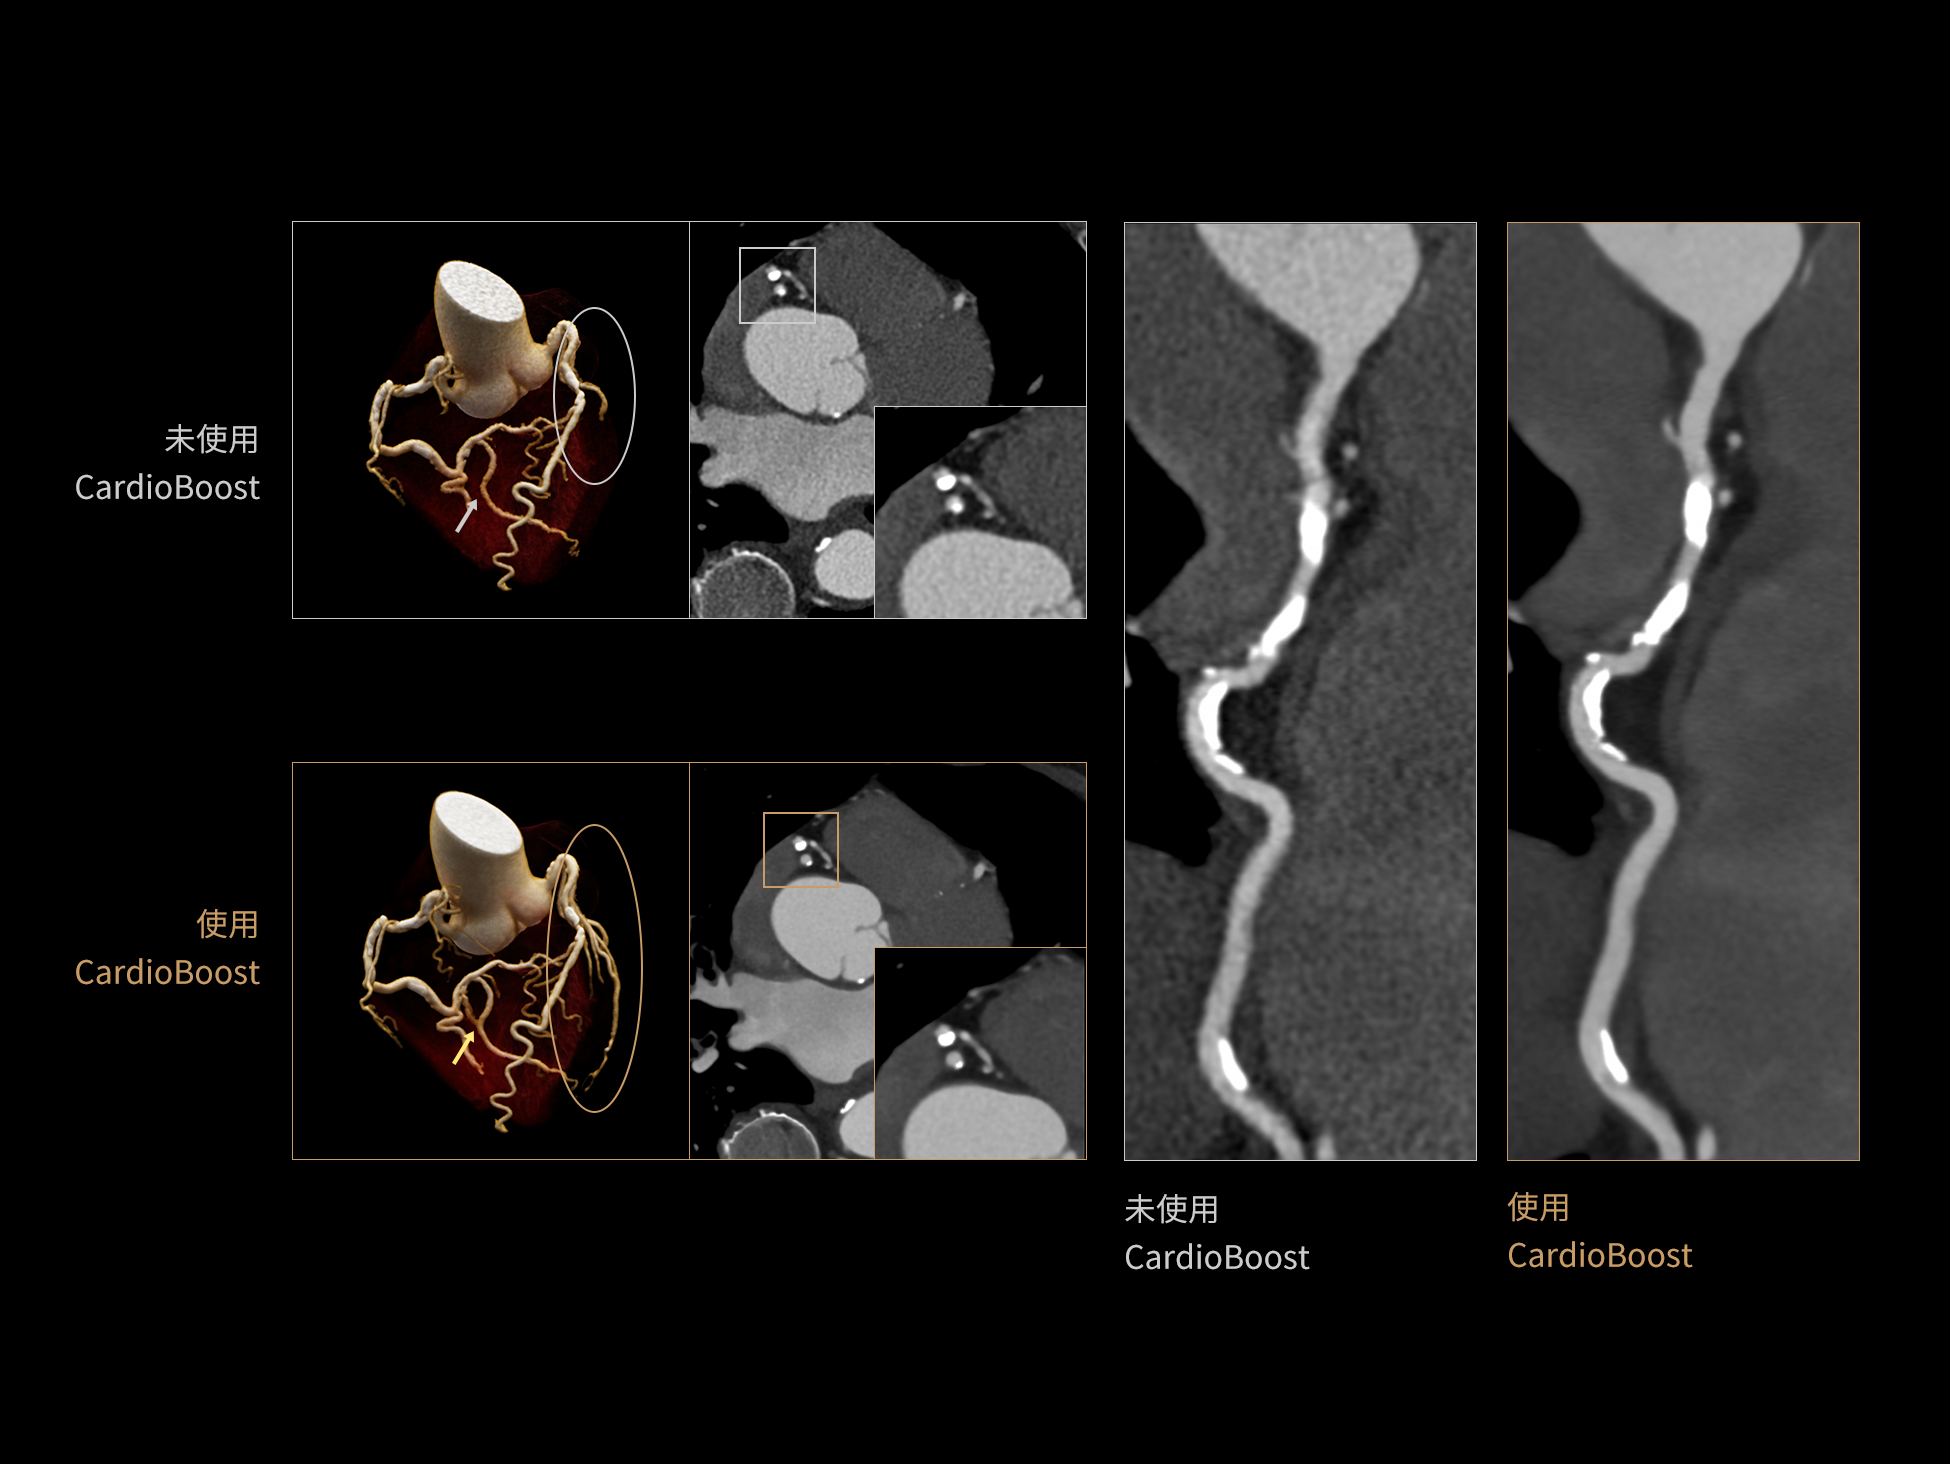

低对比度分辨率提升

相同辐射剂量下